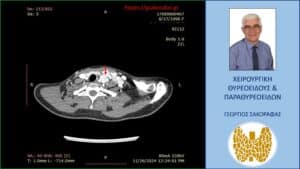

Τα ευρήματα του υπερηχογραφήματος επιβεβαιώθηκαν σε αξονική τομογραφία τραχήλου την οποία προσκομίζει η ασθενής (είχε γίνει πριν το υπερηχογράφημα) (βλ. εικόνες).

Αξονική τομογραφία – απεικόνιση σε εγκάρσια διατομή. Το βέλος έχει τοποθετηθεί στην περιοχή όπου εντοπίζονται οι παθολογικοί τραχηλικοί λεμφαδένες (ευρίσκονται εκατέρωθεν του βέλους, που έχει τοποθετηθεί ενδεικτικά).

Ανάλογη με την προηγούμενη απεικόνιση στην αξονική τομογραφία, σε διαφορετικό επίπεδο εγκάρσιας διατομής.